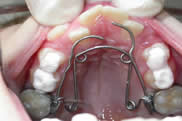

Voici des cas de patients ayant eu recours aux traitements d'orthodontie que nous proposons.

Chaque cas est particulier, c’est là toute la valeur d’une vraie consultation, qui seule pourra vous apporter la réponse adaptée à votre cas.